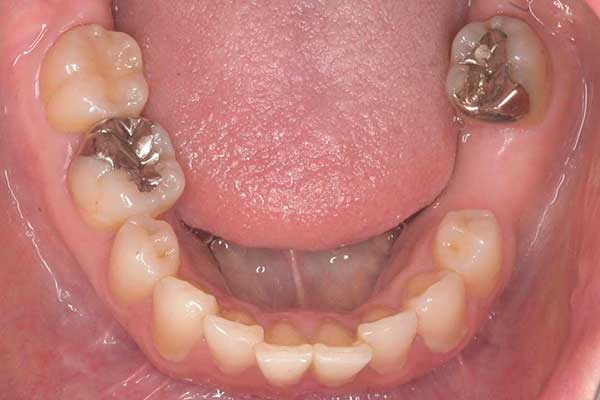

⑥ インプラント治療とセラミック治療とダイレクトボンディング

治療前

治療後

年代・性別

30代女性

お悩み

全体的に治療したい

治療内容

インプラント治療

セラミック治療

ダイレクトボンディング

治療期間・回数

1年

費用

約100万円

リスク・副作用

インプラント手術には合併症が起きる場合があります。

修復物は破損することもございます。

治療により痛みが出ることもございます。